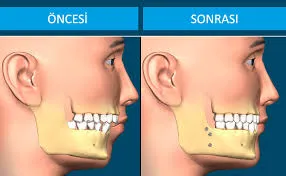

Ortognatik Cerrahi: Çene Bozukluklarının Estetik ve Fonksiyonel Çözümü